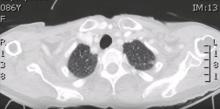

Left VATS Hemidiaphragm Traumatic Rupture Repair [1]

Diaphragmatic lacerations are not uncommon after blunt thoraco-abdominal trauma following traffic accidents. Diagnosis can be difficult as clinical presentation is sometimes unclear. VATS is a safe approach to confirm the diagnosis and treat the condition. This video presents the case of an 86-year-old woman with a grade IV injury.